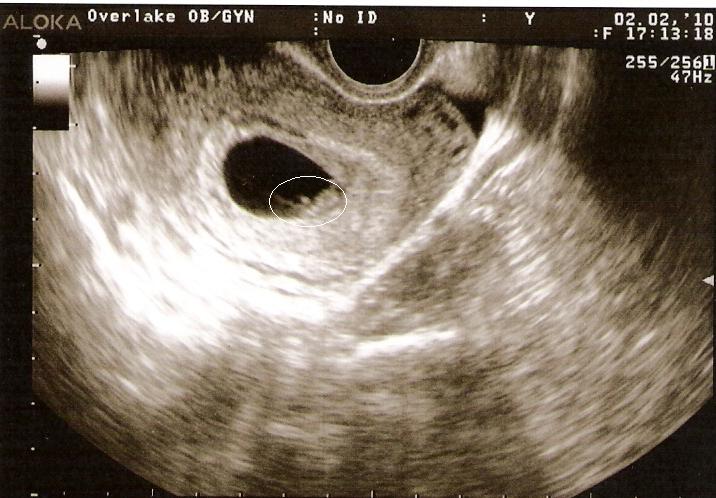

We had our first doctor appointment on February 2nd, with an ultrasound to see the baby’s heartbeat. I had my prenatal blood work done, too. Our next ultrasound is March 8. Here’s Baby 2, circled, at seven weeks. Baby Keene #2 is much bigger now: about the size of a kumquat.